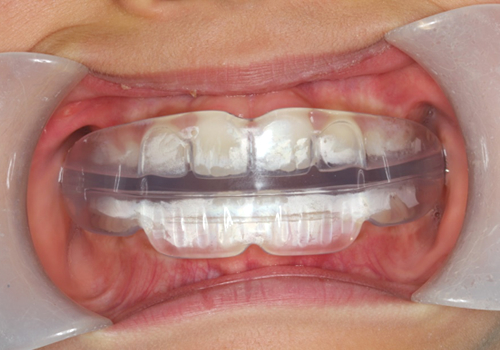

症例04. FKO

レジンブロックと唇側線からなります。

下あごを前に出した位置で噛んでいただき、下顎頭という下あごの骨の成長を促します。

| 治療内容 | 1:下あごがひけており、出っ歯に見える 2:装着時は下あごが前方に位置する 3:下あごの成長により噛み合わせが変化した |

|---|---|

| 期間 | 1年~2年 |

| 費用 | 300,000円+税 |

| リスク | 顎に違和感でる可能性もありますが、都度調整をはかっていきます。 |